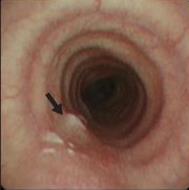

• 侵袭性肺真菌病的支气管镜表现及介入治疗效果

2025, 31(9):81-90. DOI: 10.12235/E20250317

摘要 (112) HTML (56) PDF 6.06 M (77) 评论 (0) 收藏

摘要:目的 探讨侵袭性肺真菌病(IPFD)的支气管镜表现,并评估介入治疗的安全性和疗效。方法 回顾性分析2018年5月12日-2025年5月12日于该院行支气管镜检查的35例IPFD患者的临床资料,观察IPFD的支气管镜表现及介入治疗效果。结果 共收集35例患者临床资料。其中,男22例,女13例,患者年龄(53±14)岁。基础疾病包括:血液系统恶性肿瘤10例,长期应用糖皮质激素者5例,2型糖尿病者4例,肺部恶性肿瘤2例,器官移植1例。胸部CT显示:肺部病变累及单肺叶者19例,累及多肺叶者16例。支气管镜下表现主要为:黏膜充血水肿29例(82.9%)、坏死物堵塞管腔22例(62.9%)、大量黏稠脓性分泌物17例(48.6%)、支气管部分狭窄或闭塞16例(45.7%)、黏膜坏死9例(25.7%)、黏膜出血5例(14.3%)、真菌球3例(8.6%)。其中,32例(91.4%)接受全身性抗真菌治疗,17例(48.6%)接受支气管镜局部两性霉素B灌注治疗,10例(28.6%)采用活检钳钳除病灶,6例(17.1%)采用冷冻探头冻取病灶,4例(11.4%)接受氩气刀治疗。28例(80.0%)临床症状明显改善,肺部影像学病灶缩小或消退;4例(11.4%)病灶稳定;3例(8.6%)未完成治疗。结论 IPFD多见于免疫抑制宿主,支气管镜常表现为:坏死物堵塞管腔、伴脓性分泌物、支气管管腔狭窄和局部黏膜充血水肿或坏死。全身抗真菌药物联合支气管镜下介入治疗,安全性高,且疗效好。